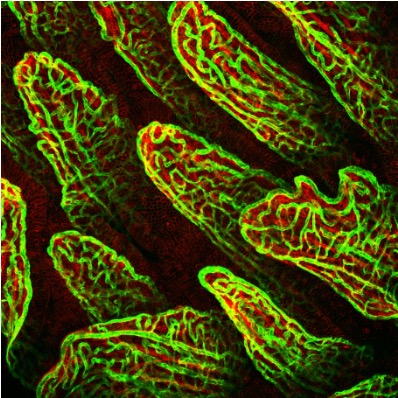

2. In Vivo Fate of Drug Delivery Systems

We systematically investigate the in vivo behavior and fate of drug delivery systems using advanced imaging and analytical tools, including intravital fluorescence microscopy, transmission electron microscopy, and synchrotron radiation-based imaging. Our studies focus on how delivery systems interact with physiological and immune barriers, such as the mononuclear phagocyte system (especially in the liver and spleen), vascular endothelium, and immune cell subsets. We analyze circulation kinetics, biodistribution profiles, cellular uptake mechanisms, and clearance pathways to elucidate the principles that govern delivery efficiency and target-site accumulation. These mechanistic insights guide the rational optimization of carrier design to improve therapeutic precision and minimize systemic toxicity.